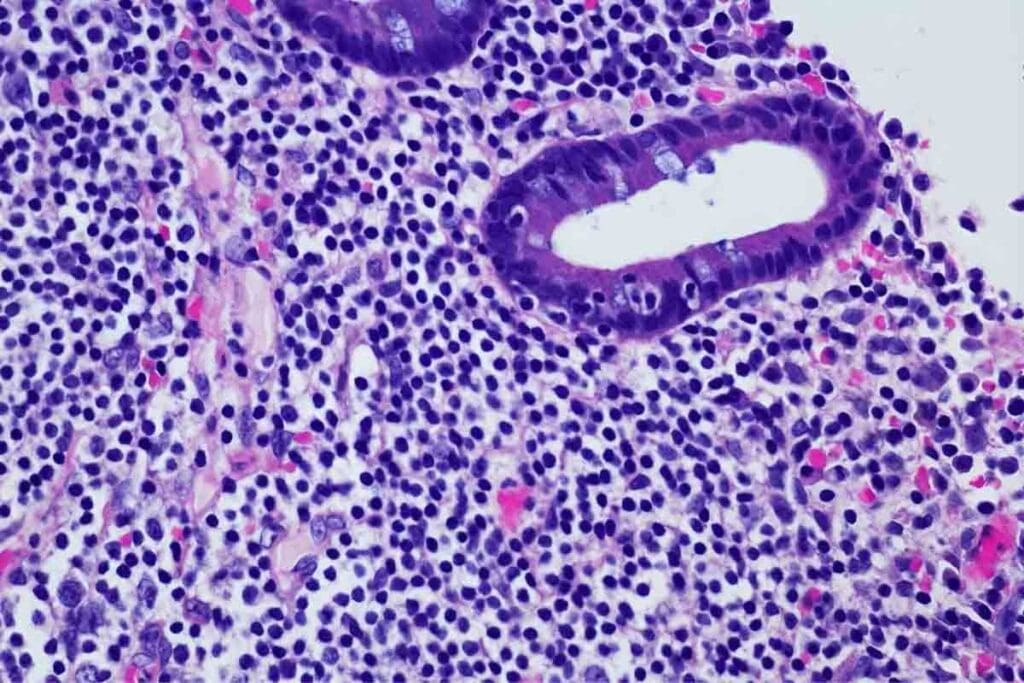

Definition and Pathophysiology of ALL

ALL is a cancer of the blood and bone marrow. It starts with a mutation in a single stem cell. This leads to the production of abnormal lymphoblasts.

These immature cells take over the bone marrow. They crowd out the healthy cells. This stops normal blood cell production.

The cells in ALL can’t grow into working lymphocytes. This means there’s not enough of the right blood cells. This includes red blood cells, platelets, and mature white blood cells.

Bone Marrow Biopsy and Cellular Analysis

A bone marrow biopsy is a key test for ALL. It takes a bone marrow sample, usually from the hip, to look at cells under a microscope. This helps find leukemia cells and learn about them.